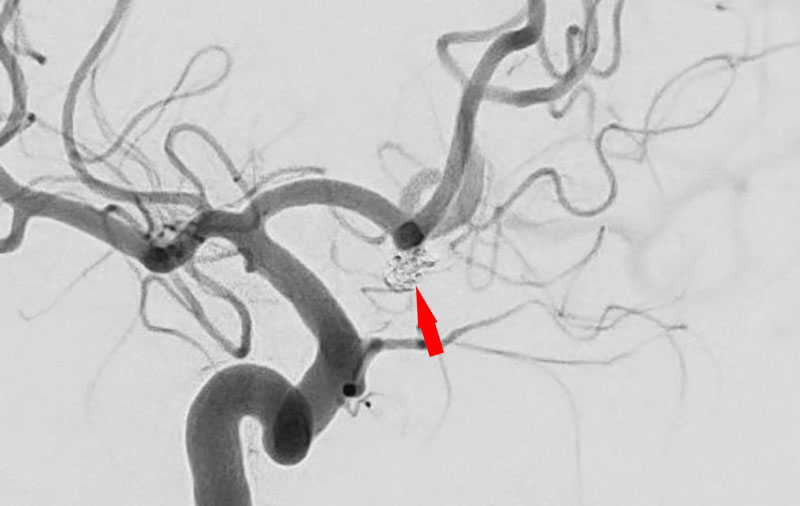

No.1630 手術前